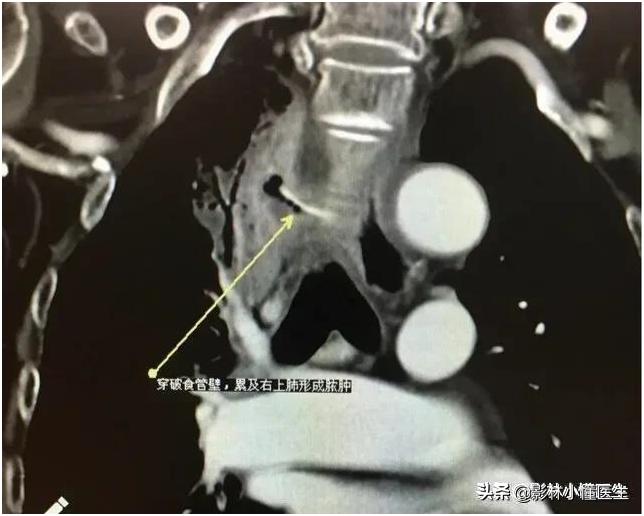

例1

食管穿孔继发纵隔及肺部感染;纵隔感染位置深,治疗困难大,部分患者发生脓毒血症,威胁生命。